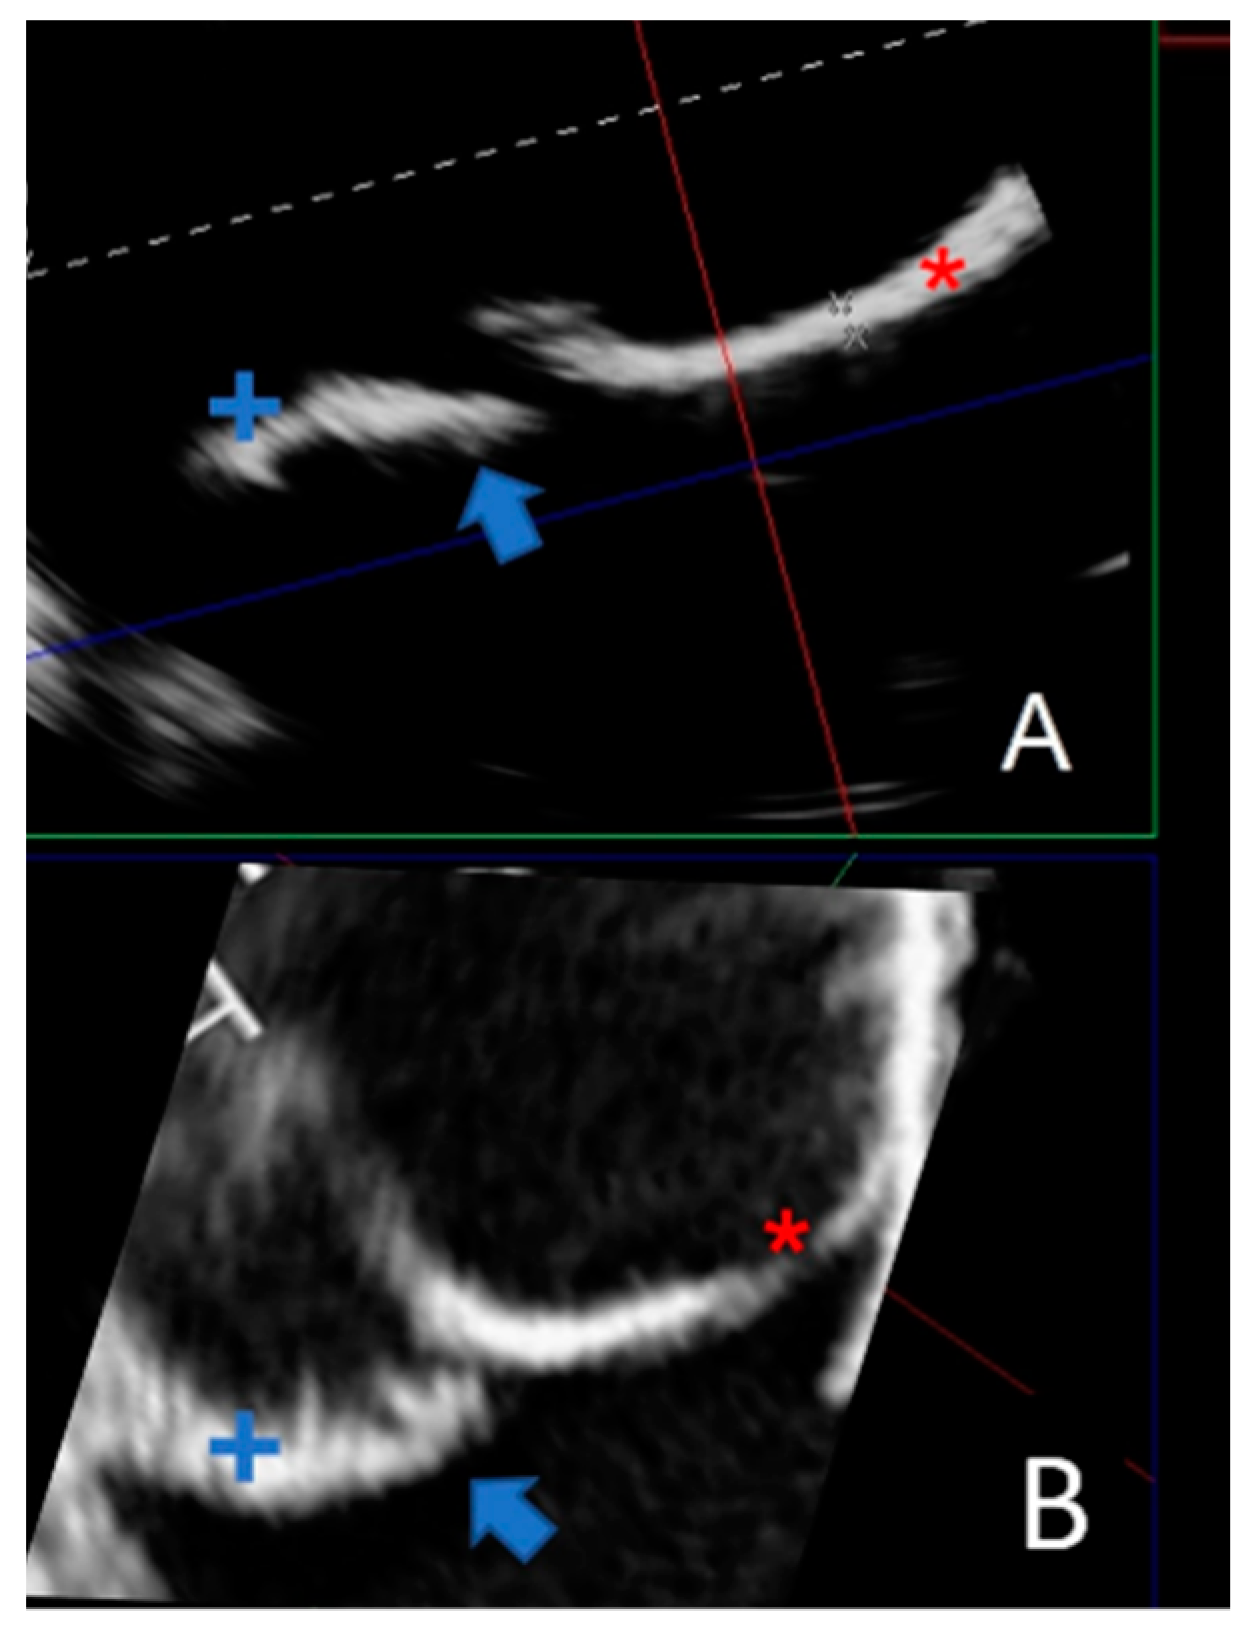

Due to their porous structure, the TPU and TPE models exhibit interesting echogenic properties. We compared the echogenic rendering with in situ images of the same valve (refer to Figure 9 and Figure 10). The valve structure was accurately depicted in both 3D and 2D views. Notably, the cusp in situ thickness measurements align with the model’s 0.3 mm thickness.

Figure 10.

Comparing a 2D echographic view of the bicuspid aorta model to the in situ view. (A) A 2D ultrasonograph of an immersed bicuspid aorta model with two cusps (+ and *) and prolapse of one cusp (blue arrow). (B). A 2D in situ ultrasound in the same orientation as A, with two cusps (+ and *) and cusp prolapse (blue arrow).